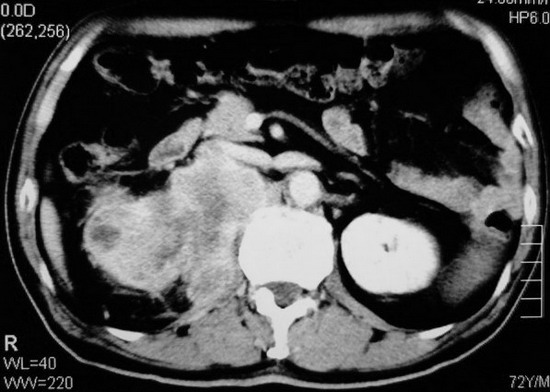

以下是引用杀毒软件在2008-11-17 19:15:00的发言:[br]考虑------右肾癌合并肾静脉---同侧肾上腺受侵可能性大

以下是引用zjzjr在2008-11-17 20:45:00的发言:[br]考虑------右肾癌合并肾静脉---同侧肾上腺受侵可能性大及腹膜后淋巴结转移.